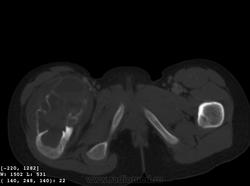

Девочка 9 лет. Родители отмечают, что 2 месяца назад девочка начала предъявлять жалобы на боли в правой пятке. Обследовались, патологии в стопе не нашли. Ребёнок постепенно начал хромать. А несколько дней назад обнаружили припухлость в в/3 бедра. Болей в бедре нет, как ночных, так и дневных. Температура не повышалась. Обратились за помощью - выполнены рентгенограммы, затем - КТ.

Злокачественная опухоль - виден луковичный периостит, инвазивный рост с лизисом кости. Но какая? Вроде бы растет из костного канала. Остеосаркома? Юинг? для этих опухолей структура какая-то больно хрящевая, мягкотканная. Хондросаркома? В таком возрасте? Почему нет клиники злокачественной опухоли кости, прежде всего - болей?

Согласна. Только периостит не луковичный, четкий лизис с козырьками Кодмена-явный признак злокачественности. А насчет болей, действительно в жизни всякое бывает, но, думаю, что ребенок не может отличить их от болей в пятке (!), а прихрамывание может быть и следствием щажения конечности.

Коллеги, давайте правильно применять термины. Периостит - окончание воспаления, применяется при остеомиелите. При опухоли - периостоз - окончание избытка, продуктивного процесса. Здесь есть "козырек Кодмена", спикулообразный периостоз, но есть так же луковичный (слоистый) периостоз, который хорошо виден на отдельных КТ-срезах. Другое дело, что для диф. диагноза опухоли (то что процесс агрессивный - сомнений не вызывыает) это, по большому счету, ничего не дает. Однако, обратите внимание на вздутие. Считаю возможны варианты телеангиоэктатической или гигантоклеточной остеосаркомы. Так же не считаю возможным исключить саркому Юинга.

+ Не потому ,что не согласен с остальными,просто не хочется девчонке "зла " ,а ,кстати на аксиальном срезе -горизонтальные уровни есть ,или это мне кажется ?-Если есть -тогда может быть и впрямь АКК?

Вы правы, коллега, мне тоже видятся уровни. Но если АКК, откуда периостоз? По КТ его оспорить сложно... По скиалогии, локализации наиболее подходит гигантоклеточная опухоль, тем более, что она часто сочетается с вторичной аневризмальной кистой. Но возраст?! хотя, чего сейчас только не бывает...